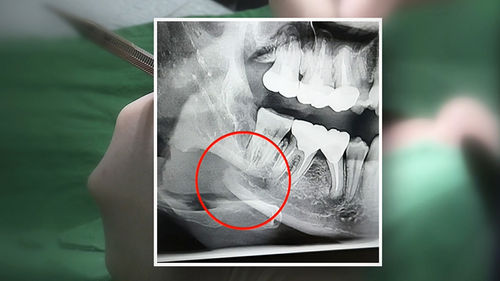

치과 치료를 하면 알 수 있는 것이 치아는 함부로 뽑지 않습니다. 정말 최대한 살려보고 그래도 안 되면 뽑아서 임플란트 등으로 빈자리를 채웁니다. 사랑니는 다른 치아들과 달리 발치를 해야 할 때도 있습니다. 잘 자란 사랑니는 특별한 문제를 일으키지 않아 뽑지 않아도 됩니다. 하지만 대부분의 사랑니는 말썽을 부립니다. 출혈, 염증, 통증 및 악취, 충치 들 여러 가지 문제를 일으킬 확률이 높기 때문에 뽑아야 합니다.